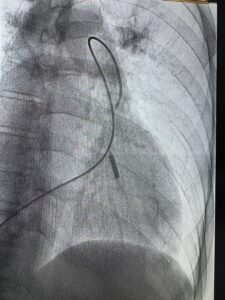

“Під час втручання ми через стегнову вену спеціальним катетером дісталися звуженої легеневої артерії та за допомогою балона відновили прохідність судини. Такі операції ми виконуємо під контролем КТ, тому одразу бачимо результат – як поліпшується кровотік і знижується тиск”, — пояснює Василь Процько, завідувач відділення кардіології та реперфузійної терапії Центру серця і судин Лікарні Святого Пантелеймона.

Перша для спеціалістів Першого медоб’єднання Львова балонна ангіопластика легеневих артерій минула успішно. Це відкриває можливість порятунку для сотень пацієнтів, яким раніше могли хіба що полегшити симптоми.